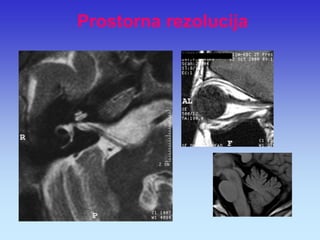

Prostorna rezolucija